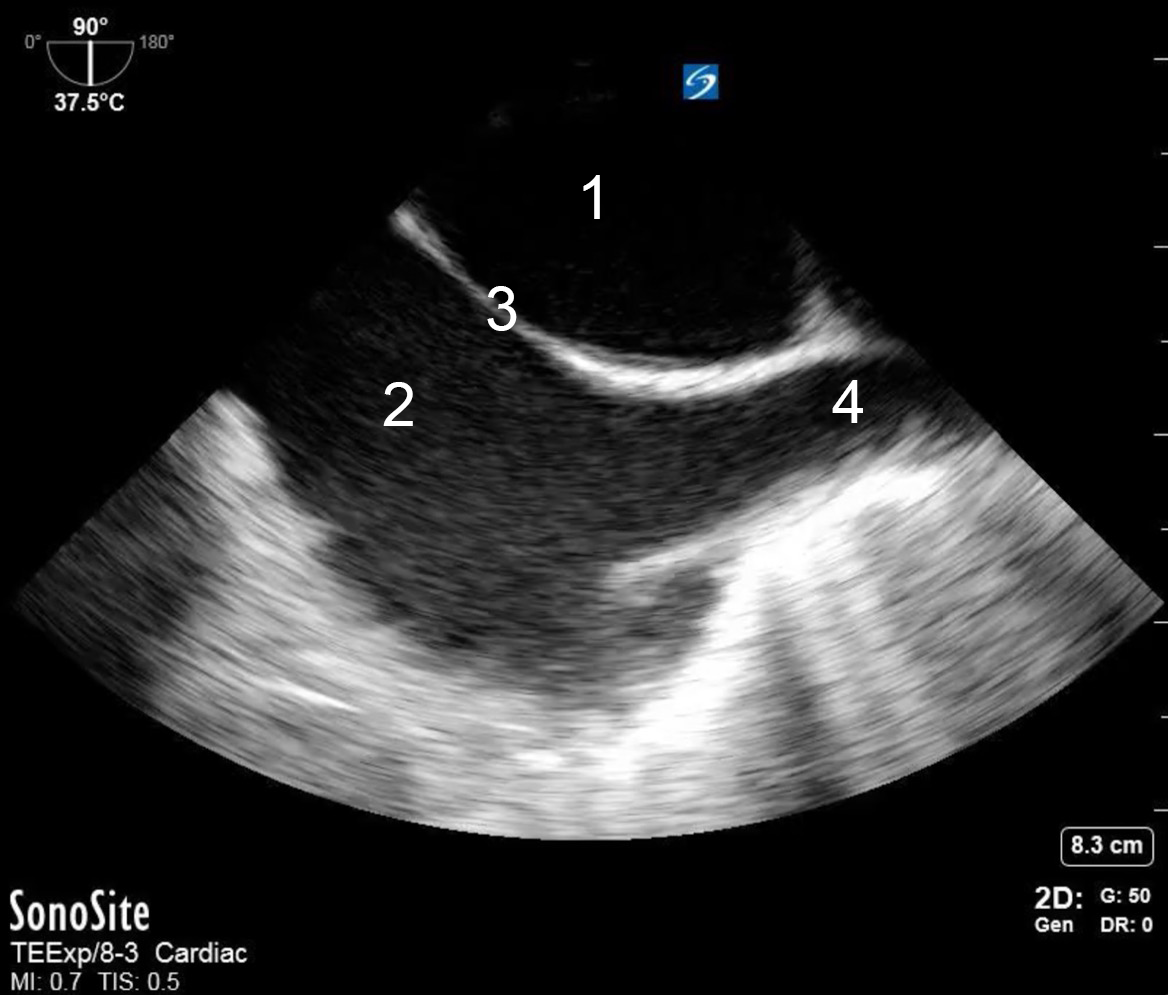

TEE Resus Mid-esophageal Bicaval Image

1. Left Atrium

2. Right Atrium

3. Interatrial Septum (IAS)

4. Superior Vena Cava (SVC)